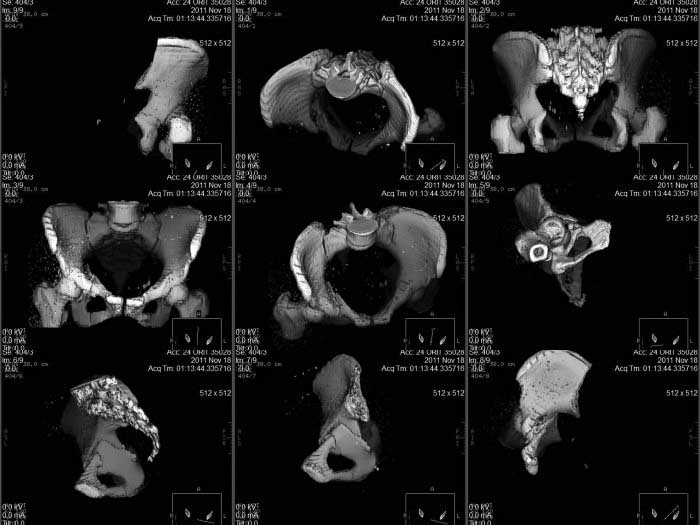

Кт снимки

КТ срезы помогают увидеть мелкие фрагменты и маргинальную импакцию, но на ваших мелких срезах трудно увидеть повреждение боковой массы крестца? Классифицировать перелом вертлужной впадины по Летурнелю все таки привычнее на косых Judet снимках.

Некоторые переломы вертлужной впадины между собой трудно отличаются, и надо проводить дифференциальную диагностику переломов: Т-образного, двух колонного и комбинации поперечного с переломом задней стенки (Associate

Transverse &Posterior Wall). Отсутствие вовлечения крыла подвздошной кости при двухколонном и наличие перелома в седалищной кости говорит о

Т-образном переломе.